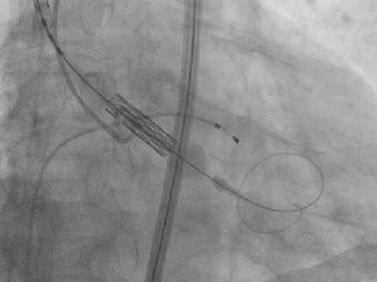

术中关键步骤影像:

25mm球囊预扩

29mm S3瓣膜-3cc释放